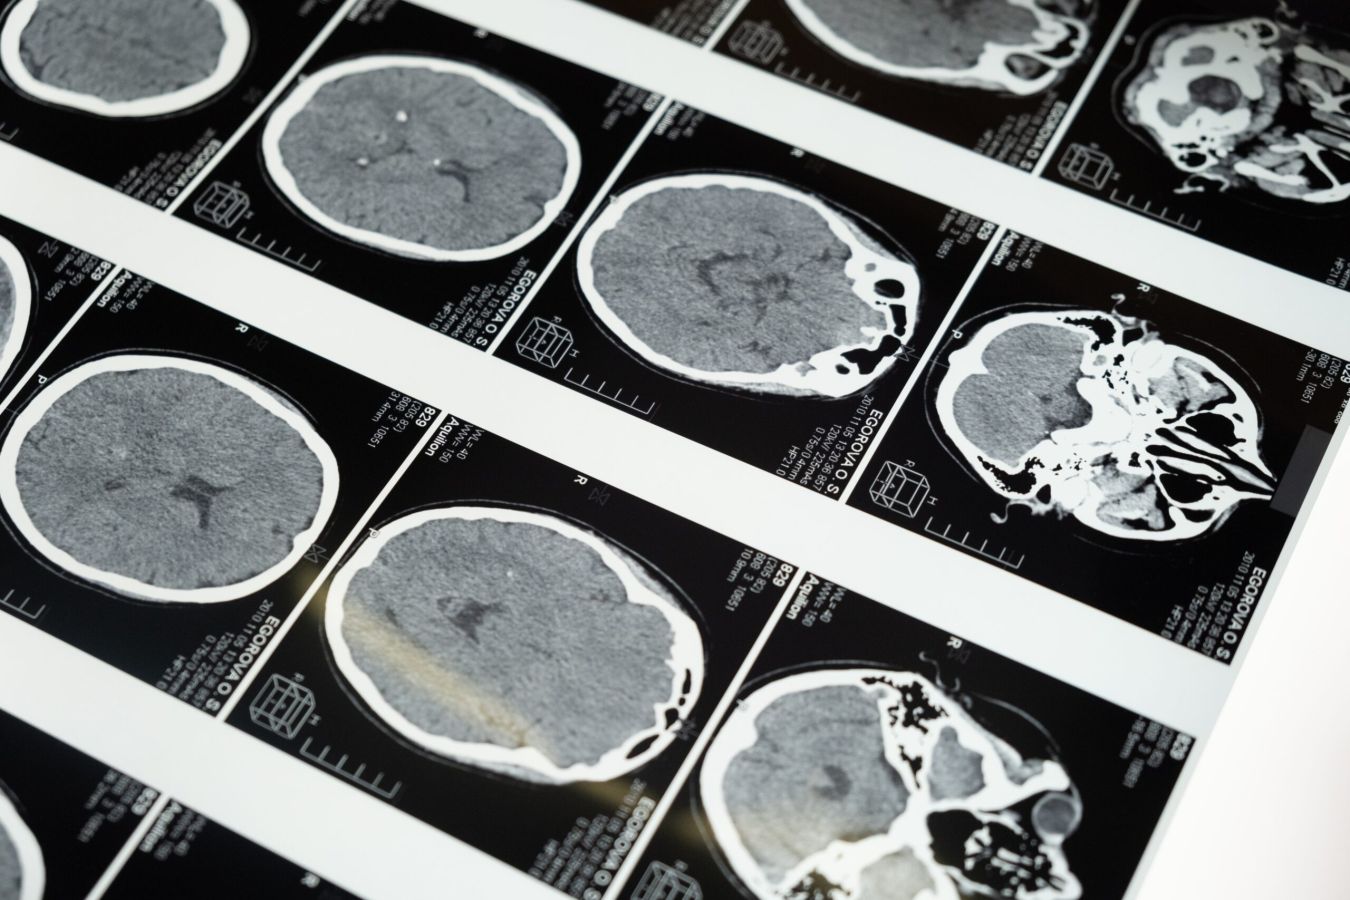

We organiseren een informatiebijeenkomst over omgaan met gevolgen van een herseninfarct, hersenbloeding, TIA, ongeluk met hoofdletsel of hersenoperatie. Tevens gelegenheid tot lotgenotencontact en het stellen van vragen.

Het thema is deze keer: Depressieve gevoelens bij NAH. Sanne Pelser (neuropsycholoog, Basalt) gaat in op dit onderwerp en zal uw vragen beantwoorden. Ad van Dongen, (ervaringsdeskundige) zal ook aanwezig zijn. Het is voor mensen die een herseninfarct, hersenbloeding, TIA, ongeluk met hoofdletsel of hersenoperatie hebben (gehad). Recent of langer geleden. Ook mensen met MS/Parkinson, familieleden en andere geïnteresseerden zijn welkom. Het is op dinsdag 31 mei om 19.00-20.00 uur digitaal via ZOOM.